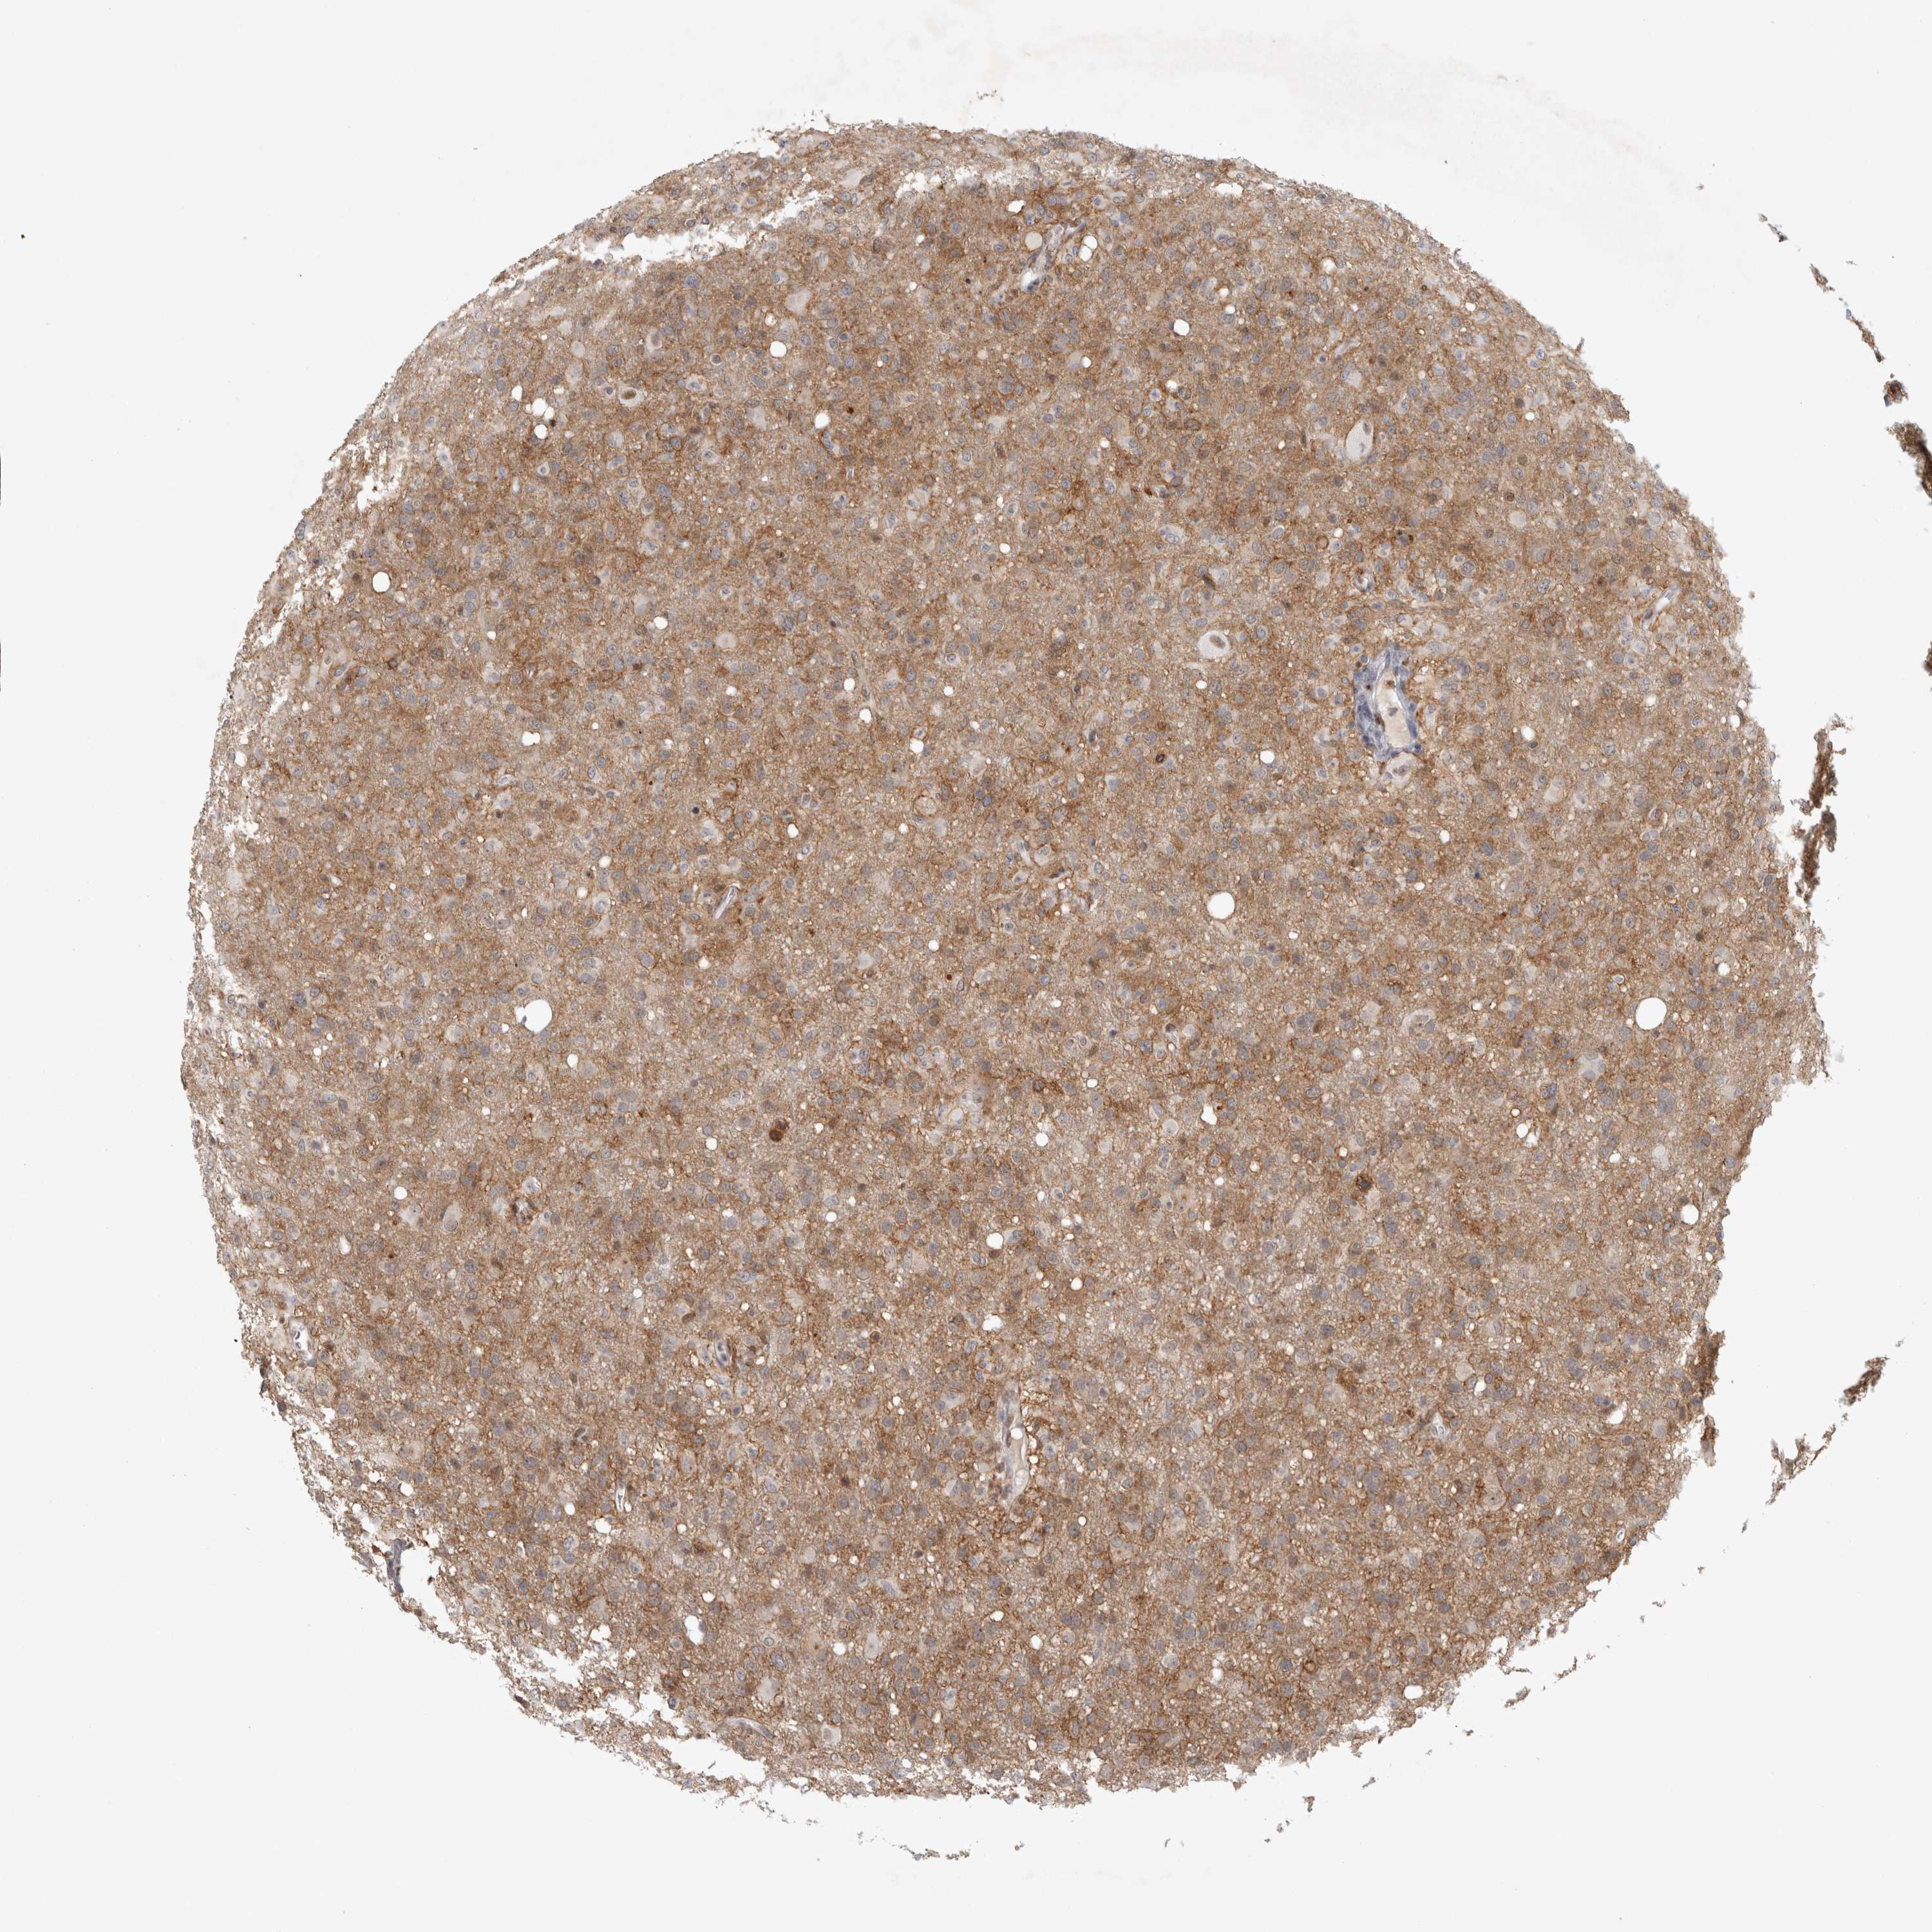

GLIOMA - Protein expressioni

A mouse-over function shows sample information and annotation data. Click on an image to view it in a full screen mode. Samples can be filtered based on level of antibody staining by selecting one or several of the following categories: high, medium, low and not detected. The assay and annotation is described here.

Note that samples used for immunohistochemistry by the Human Protein Atlas do not correspond to samples in the TCGA dataset.

Antibody stainingi

Antibody staining in the annotated cell types in the current human tissue is reported as not detected, low, medium, or high, based on conventional immunohistochemistry profiling in selected tissues. This score is based on the combination of the staining intensity and fraction of stained cells.

Each image is clickable and will lead to virtual microscopy that enables deeper exploration of all samples and also displays staining intensity scores, fraction scores and subcellular localization as well as patient and tissue information for each sample.

Antibody HPA026676

Staining

High

Medium

Low

Not detected

Intensity

Strong

Moderate

Weak

Negative

Quantity

>75%

75%-25%

<25%

None

Location

Nuclear

Cytoplasmic/membranous

Cytoplasmic/membranous,nuclear

Glioma, malignant, High grade

Glioma, malignant, Low grade